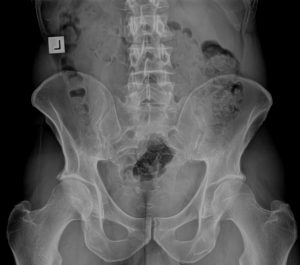

The objective of chiropractic is to correct joint dysfunction (subluxation). The use of x-ray can be important in chiropractic management, especially with the gonstead system, which aims for specific identification of the biomechanics of a sacro-iliac issue, and precise correction.

Once the specific nature of the Sacro-iliac subluxation is identified, the adjustment can then proceed. The goal is precise correction of the subluxation to restore normal function.